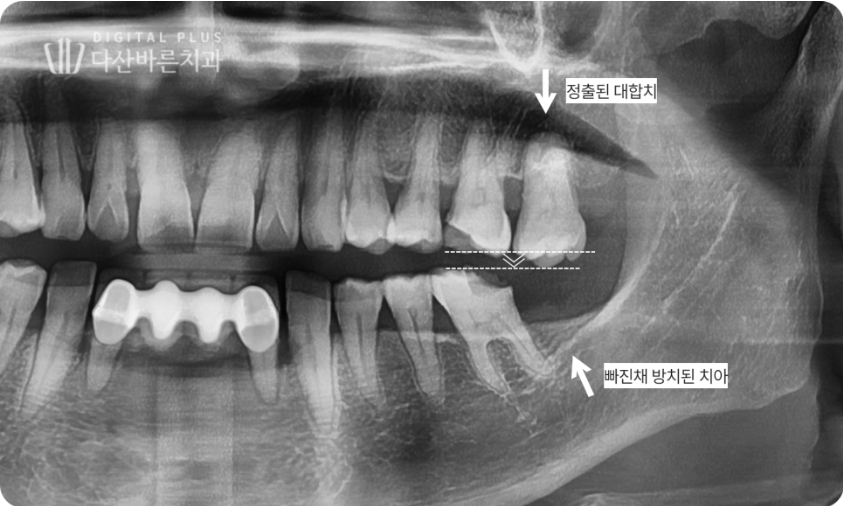

두 번째 환자분 케이스입니다. 해당 환자분은 좌측 아래 가장 끝 어금니가

빠진지 오래된 상태셨는데요. 이로 인해 마주하고 있는 위쪽 대합치가

아래쪽으로 정출된 상태가 확인됩니다.

▲ 초진 시 구강 사진. 왼쪽 아래 어금니를 빠진 채 방치하여 위 대합치가 정출된 상태.